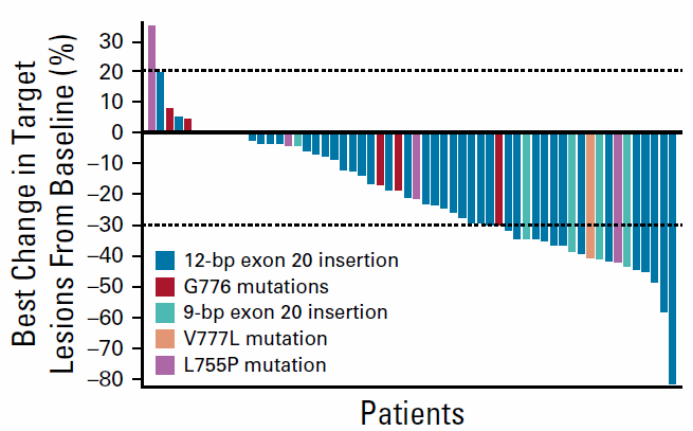

近日,上海市交通大学附属胸科医院陆舜教授作为第一作者兼通讯作者在《柳叶刀·呼吸医学》(The Lancet Respiratory Medicine, IF=30...

乳腺癌是女性最常见的恶性肿瘤,全球每年新发病例约226万例,占所有女性新发癌症总数的24.5%。尽管化疗及靶向治疗等多种治疗方式提高了乳腺癌的治愈率、延长了乳腺癌...